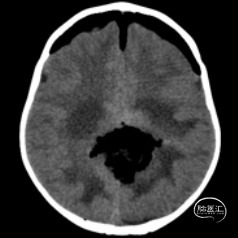

双侧额顶叶中线旁脑实质内团片状异常信号影,呈明显花环状强化,累积脑膜及胼胝体压部,性质待定,恶性胶质瘤?

非典型畸胎瘤样/横纹肌样瘤( AT /RT) 是发生在儿童中枢神经系统的少见的具有极大侵袭性的恶性肿瘤,在儿童中枢神经系统肿瘤中发病率极低。CT平扫多表现为混杂密度,也可等或稍高密度,呈不均匀或均匀强化,瘤内常可见囊性变及瘤周低密度水肿带。MRI扫描T1加权像为低信号,T2加权像为等信号或高信号,肿瘤实质与灰质信号相似或稍高,增强扫描可见中等至明显 增强,等信号时可能与肿瘤细胞密集,细胞核比例大而含水量相对较少有关。AT /RT是原发于中枢神经系统、好发于儿童、极其少见、侵袭性极高的胚胎性肿瘤,临床表 现及影像学无特异性,确诊有赖于组织病理。最大限度的安全切除,并辅以放化疗,可改善患者预后,但总体预后仍然很差。